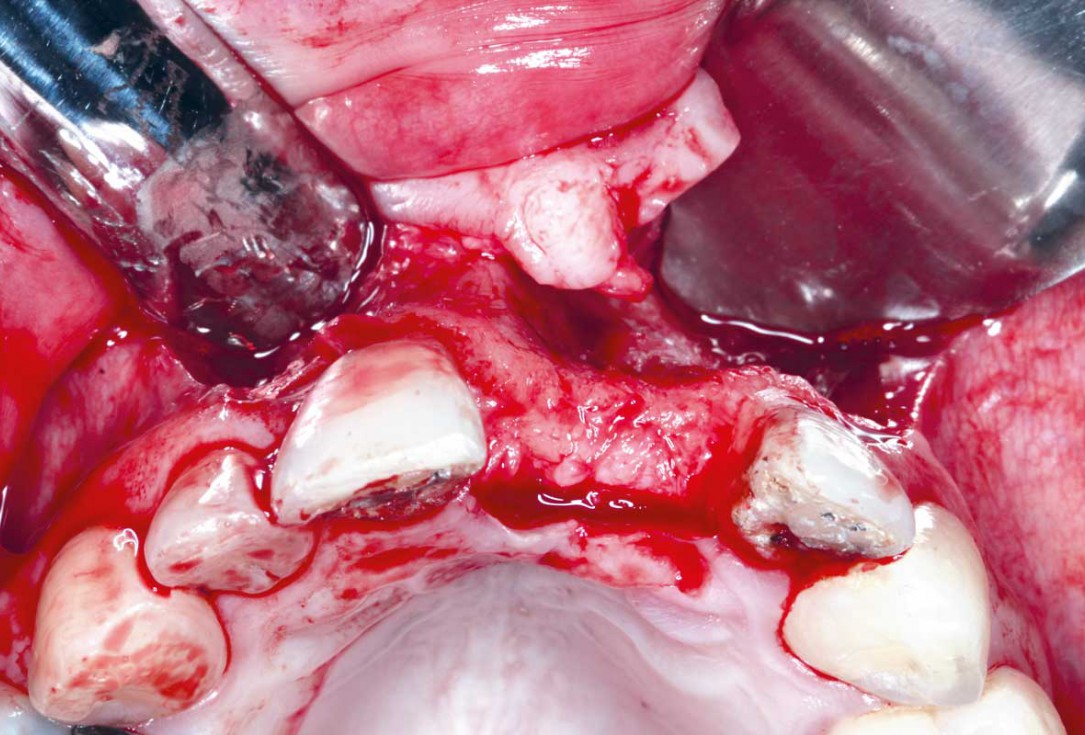

5/35 - Three-sided full thickness flap and cleaning the surgical area from the granulation tissueBlock grafting in the aesthetic zone with maxgraft®, Jason® membrane and cerabone® - Dres. H. Maghaireh and V. Ivancheva

6/35 - Three-sided full thickness flap and cleaning the surgical area from the granulation tissueBlock grafting in the aesthetic zone with maxgraft®, Jason® membrane and cerabone® - Dres. H. Maghaireh and V. Ivancheva